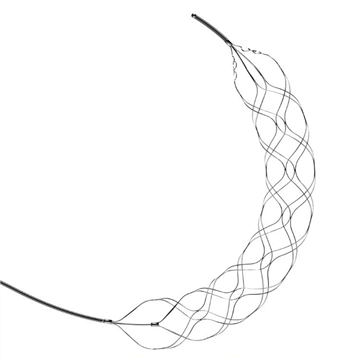

Stent Retriever de trombectomiaEls stent retrievers són dispositius endovasculars que poden eliminar els coàguls de les grans artèries en pacients amb ictus isquèmic agut. Aquests dispositius estan dissenyats per ser introduïts a t

Stent Retriever intracranialAl mercat es presenta un dispositiu recuperador de coàguls que es pot utilitzar en vasos sanguinis intracranials, que inclou un esquelet que es pot trenar a partir de cables d'aliatge amb memòria de f